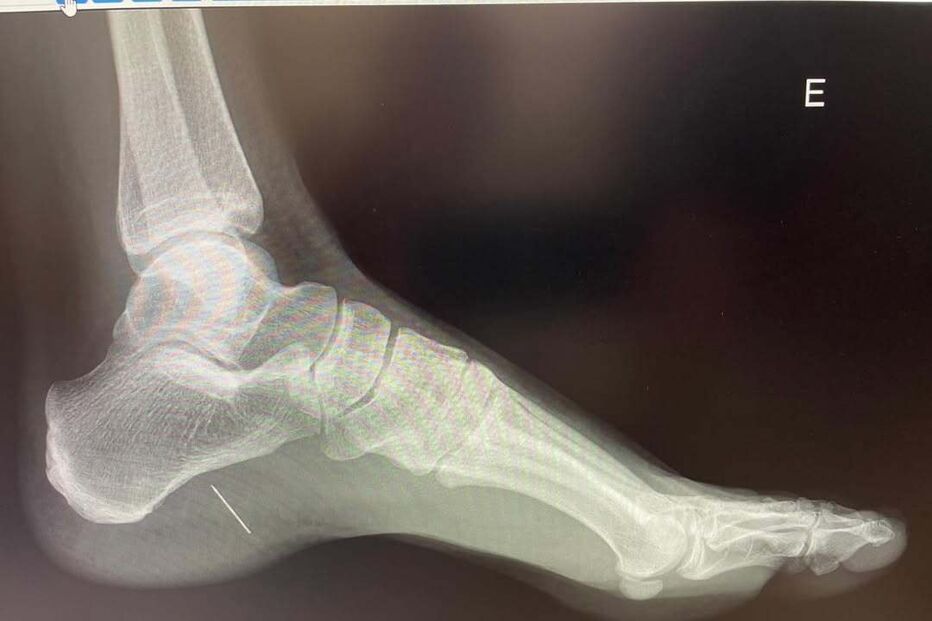

"Piquei-me no pé com um alfinete. Doeu, continuei com a minha vida mas a dor não passava. Andei de muletas sempre a achar que acordaria melhor no dia seguinte… Até que ao 7.º dia fui fazer um raio X", começou por contar a designer de vestidos de noiva no Instagram.

"Algo não estava bem. Não tinha o pé inchado, não tinha febre, não estava infetado, nem vermelho nem quente mas tinha um alfinete lá dentro! O filho da mãe ainda deu luta ao cirurgião, partiu-se mas lá saiu… Esta brincadeira deu direito a uma cirurgia em bloco operatório, anestesia geral e uma semana de repouso! NUNCA MAIS ANDO DESCALÇA", escreveu ainda, uma mensagem que valeu um recado da irmã Matilde Breyner.